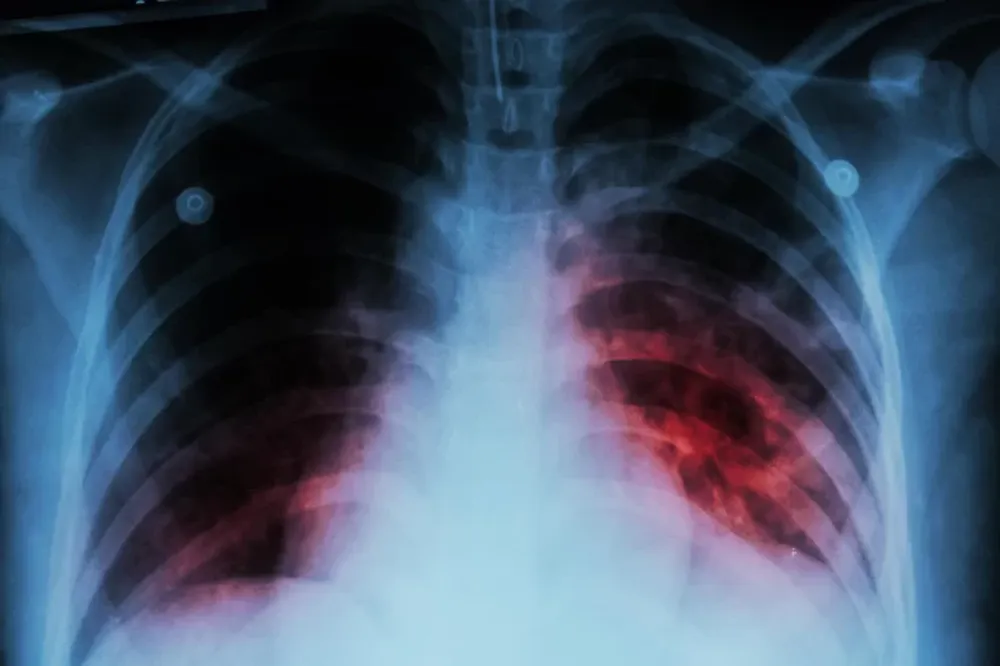

Existen diferentes pruebas para detectar la tuberculosis, como ser, la radiografía de tórax y el análisis de esputo (flema) con pruebas moleculares o cultivos y pruebas cutánea de tuberculina. Según Lagrutta, “es necesario garantizar el acceso a métodos sensibles y rápidos de diagnóstico de tuberculosis, y de resistencia a fármacos, que favorezcan un diagnóstico precoz y un oportuno inicio de tratamiento con el esquema adecuado. La OMS sugiere realizar métodos moleculares rápidos en forma universal, es decir a todos los pacientes. Estos métodos son mucho más sensibles que una baciloscopia (visualización del bacilo de Koch con el microscopio) y permiten además detectar resistencia a los principales fármacos utilizados en el tratamiento.”